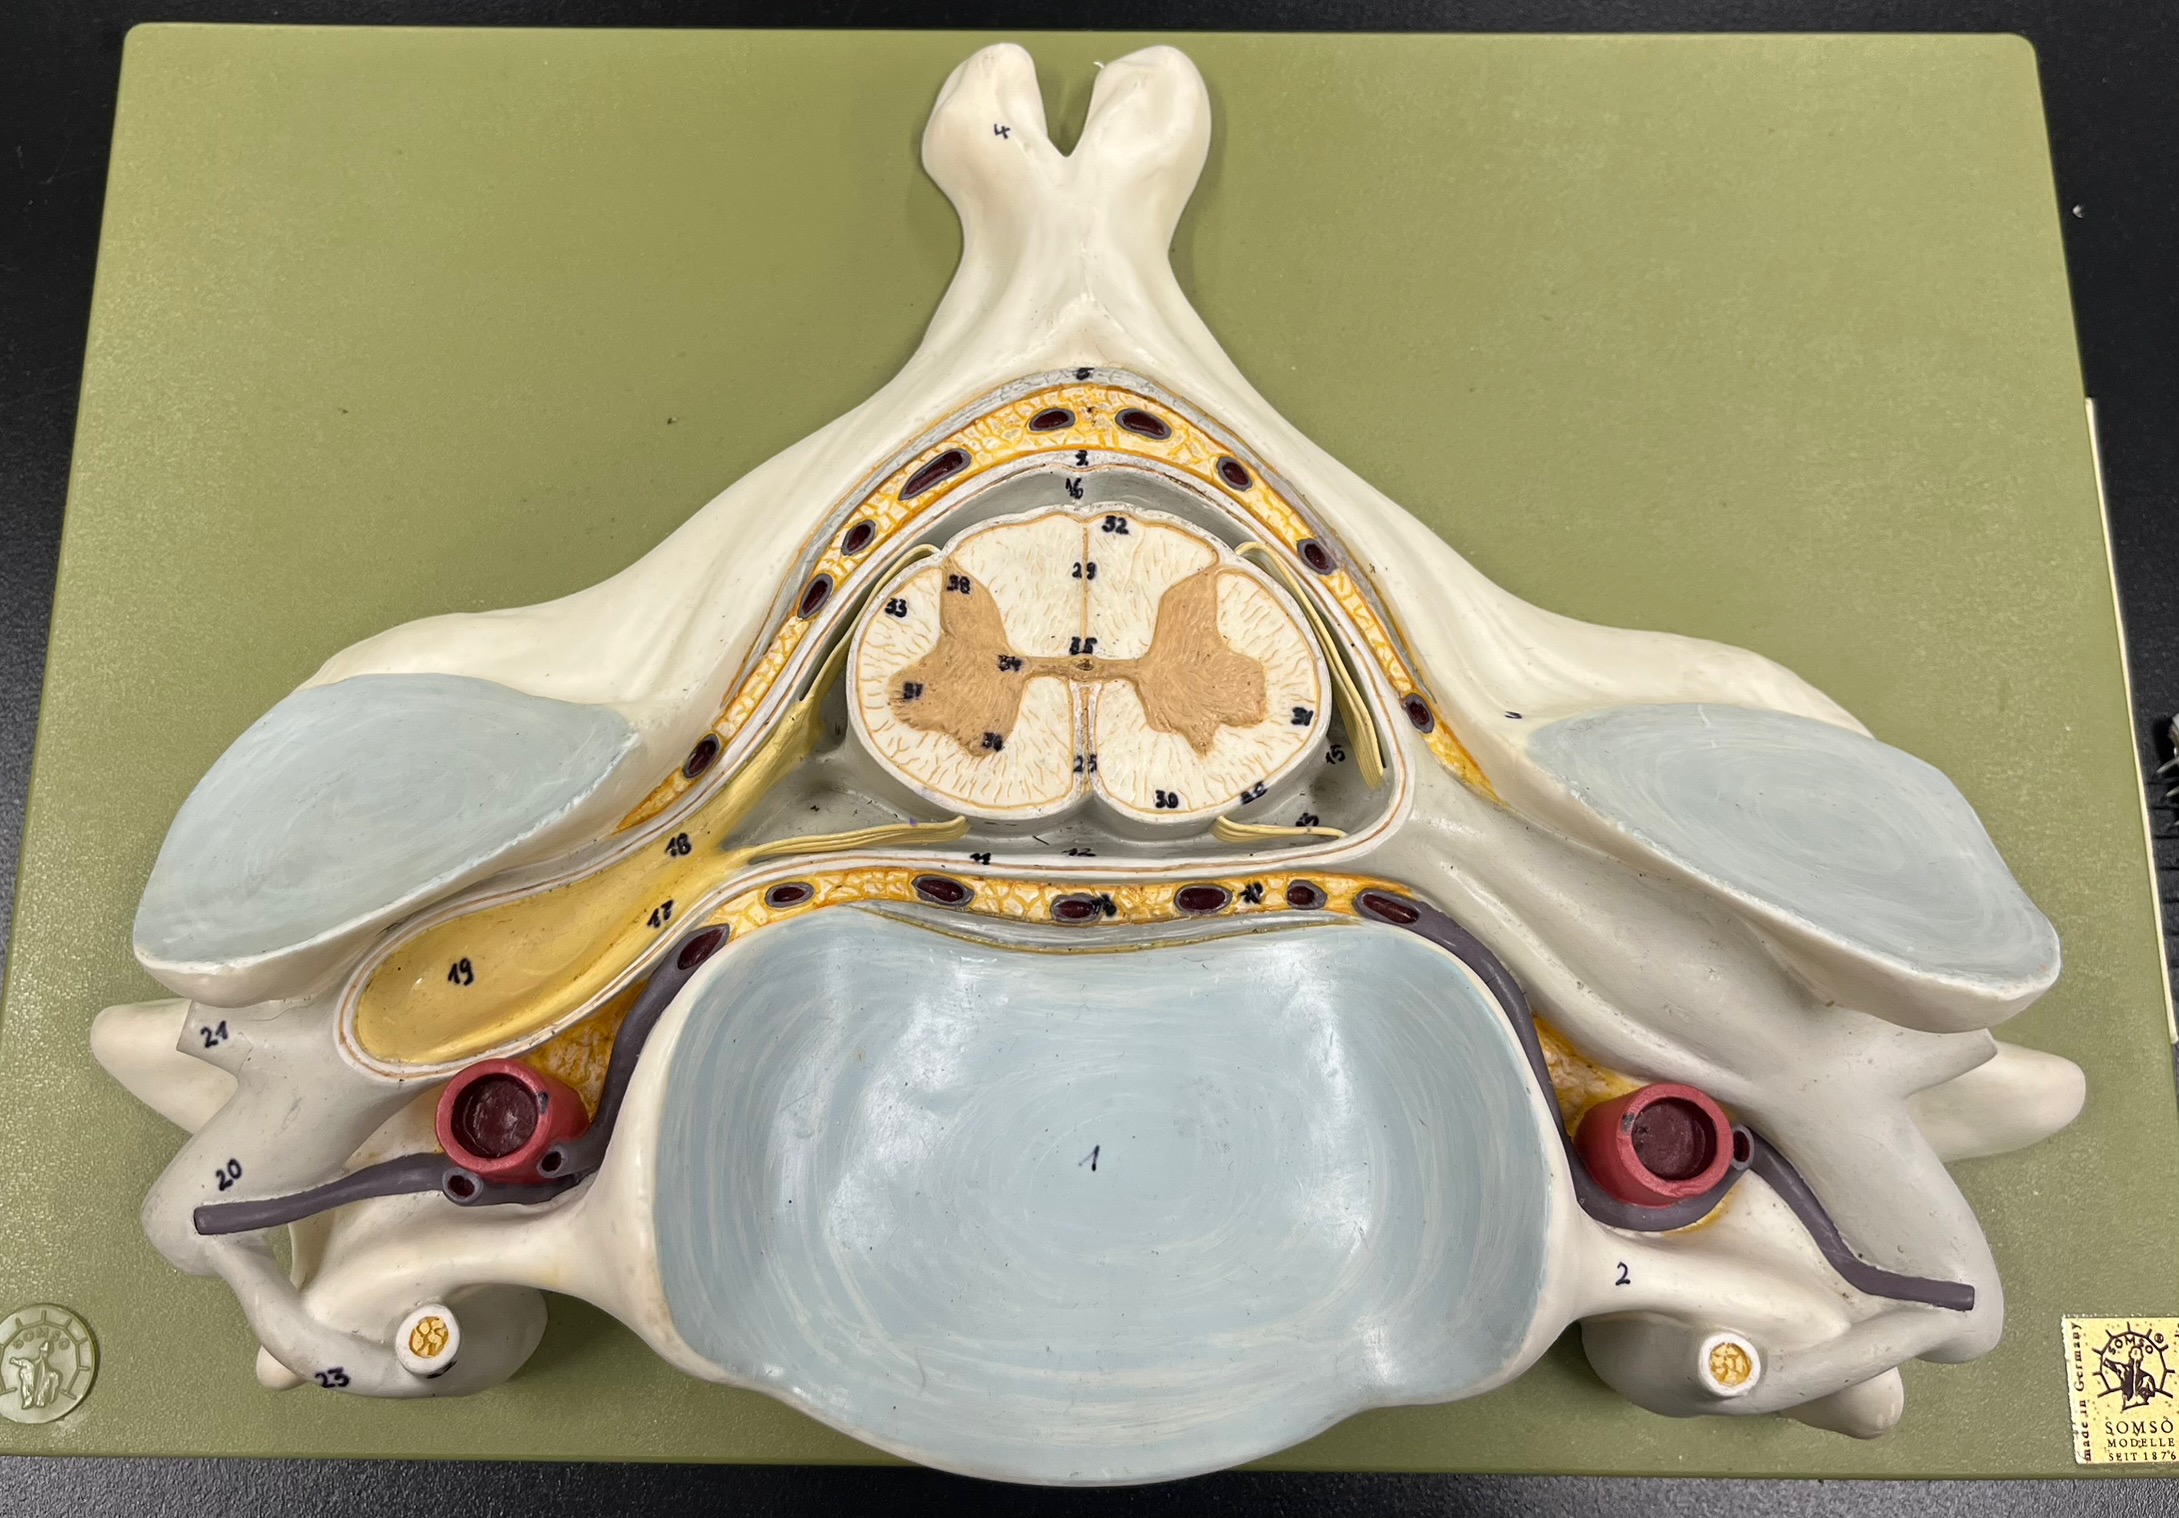

epidural space

dura mater

subdural space

arachnoid mater

subarachnoid space

pia mater

denticulate ligaments

What is the groove here?

anterior median fissure

posterior median sulcus

posterior (dorsal) horn

posterior (dorsal) horn; R—>L

anterior (ventral) horn

lateral horn (selected models)

gray commissure

central canal

anterior column

lateral column

posterior column

white commissure

posterior (dorsal) root ganglion

What is the bulb here?

posterior (dorsal) root ganglion

posterior (dorsal) root

posterior (dorsal) root

anterior (ventral) root

anterior (ventral) root

dorsal ramus

dorsal ramus

ventral ramus

ventral ramus

rami communicantes

rami communicantes

sympathetic chain ganglia

sympathetic chain ganglia